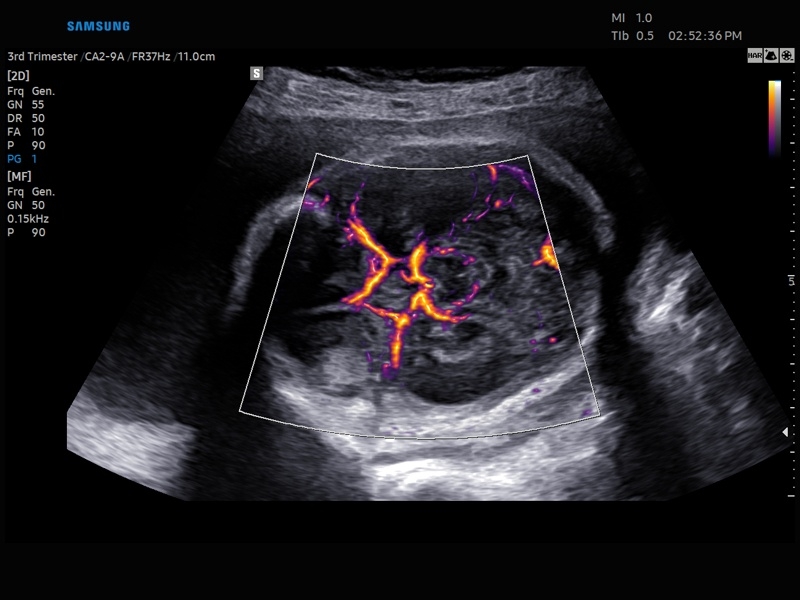

Ультразвуковой сканер V8-RUS является экспертным классом (премиальный уровень) и производится компанией Samsung Medison. Сканер V8 обеспечивает превосходное качество изображения благодаря использованию технологии Crystal Architecture™, которая включает в себя передовое аппаратное обеспечение, монокристальную технологию изготовления датчиков и сложную программную обработку ультразвуковых лучей.

• Цветной, энергетический и направленный энергетический допплер

• Smart 4D с технологиями Realistic VUE и Crystal VUE

• Контрастное усиление CEUS+

• Технологии визуализации: MV Flow, LumiFlow, SEE Stream, Panoramic

• Модуль MV-Flow – программа (режим), позволяющая визуализировать кровоток в микроциркуляторном русле с высоким разрешением без использования контраста.

• Модуль LumiFlow – программа отображения кровотока с объемной графикой для лучшего понимания архитектоники сосудистого русла.